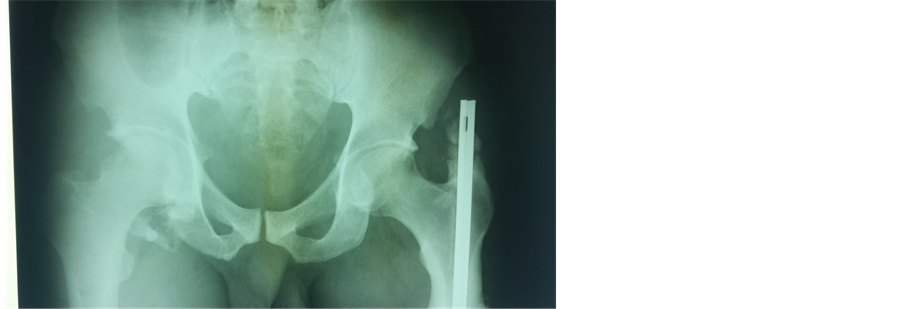

Mr. BA was a 29-year-old patient who was hospitalized in October 2000 following a road traffic accident. He was sitting behind the driver when his right knee hit the driver’s seat. On admission, the same limb was abducted, externally rotated and flexed at the hip. An anteroposterior radiograph of the pelvis revealed a right obturator dislocation (Figure 1) associated with a left supracondylar open fracture. Treatment consisted of closed reduction. The hip was stable afterward. The left supracondylar open fracture was treated surgically. Weight bearing on the dislocated limb was authorized after 6 weeks of bed traction. Thirty nine months later, the right hip is mobile, painless and normal on plain X-rays.

Figure 1. Anteroposterior X-ray of the pelvis showing a right obturator dislocation (patient 1).